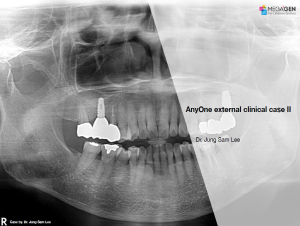

AnyRidge,Dr. Miguel Stanley,Immediate loading,Maxillary Anterior,Scientific background,Single replacement